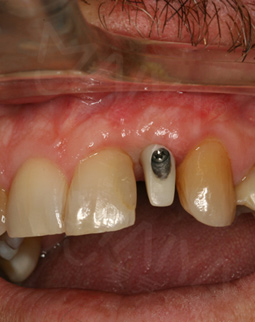

今年的4月18日,我去了第一次复诊后,直接飞回了加拿大。坐飞机过程也没有什么不适感,而且有按照郑院长的要求,一直在好好的呵护我的种植牙。现在回到中国,手机上显示客服的复诊短信提醒,虽然在还未种完牙的情况下,但这丝毫不影响我继续享用美食。复诊的时候,拍了片子,郑院长说植入的植体与骨结合不错,然后给我安装了愈合基台,说我有什么不适的话,都可以过来。

今天又来复诊,愈合基台无松动,可以戴牙冠了,取模也很方便,然后还有比色,一颗种植牙看着只是种牙而已,其实每个环节还是挺细心的,这次复诊刚好碰上活动,在此祝福生日快乐,也希望更多的缺牙人能在这里重拾口福健康!